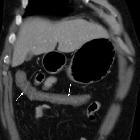

Hypovolemic

shock with subtle imaging signs: systemic capillary leak syndrome. Most of the collapsed colon showed diffuse, moderate circumferential mural thickening (thin arrows) with mucosal enhancement and mural hypoattenuation suggesting submucosal oedema.

shock with subtle imaging signs: systemic capillary leak syndrome. Diffuse, moderate circumferential mural thickening (thin arrows) with mucosal enhancement and mural hypoattenuation suggesting submucosal oedema. Note marked nephrogram, slit-like inferior vena cava (arrow).